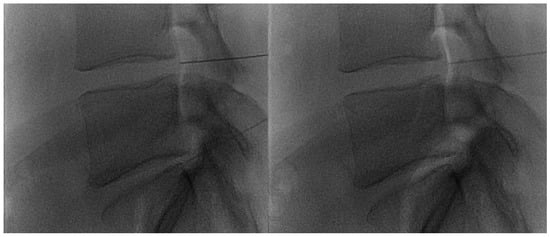

- Giurazza, F.; Guarnieri, G.; Murphy, K.J.; Muto, M. Intradiscal O2O3: Rationale, Injection Technique, Short- and Long-term Outcomes for the Treatment of Low Back Pain Due to Disc Herniation. Can. Assoc. Radiol. J. 2017, 68, 171–177. [Google Scholar] [CrossRef] [PubMed]

- Muto, M.; Ambrosanio, G.; Guarnieri, G.; Capobianco, E.; Piccolo, G.; Annunziata, G.; Rotondo, A. Low Back Pain and Sciatica: Treatment with Intradiscal-Intraforaminal O(2)-O(3) Injection. Our Experience. Radiol. Med. 2008, 113, 695–706. [Google Scholar] [CrossRef]

- Andreula, C.F.; Simonetti, L.; De Santis, F.; Agati, R.; Ricci, R.; Leonardi, M. Minimally invasive oxygen-ozone therapy for lumbar disk herniation. Am. J. Neuroradiol. 2003, 24, 996–1000. [Google Scholar] [PubMed]

- Muto, M.; Andreula, C.; Leonardi, M. Treatment of herniated lumbar disc by intradiscal and intraforaminal oxygen-ozone (O2-O3) injection. J. Neuroradiol. 2004, 31, 183–189. [Google Scholar] [CrossRef] [PubMed]